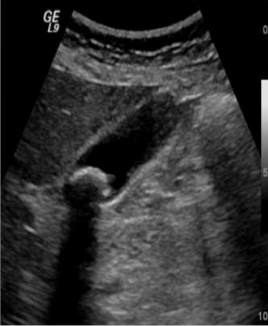

<p>Qué artefacto es más evidente?</p>

Qué artefacto es más evidente?

Sombra acústica posterior